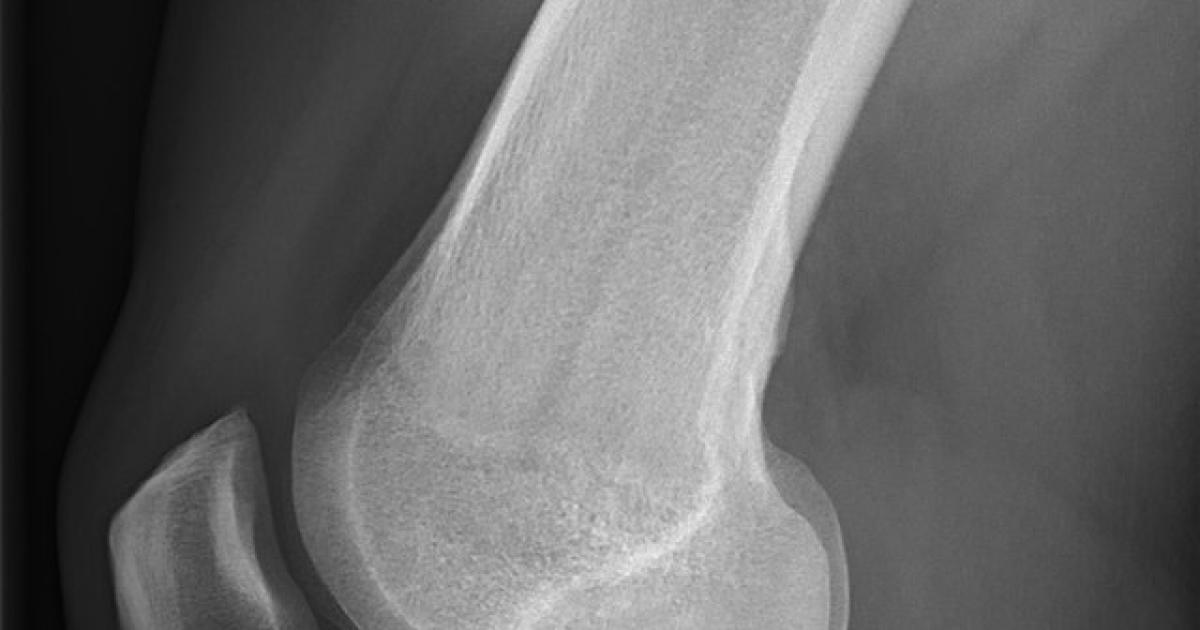

But now we have an excellent new tool. BoneScore is a direct approach to evaluating bone tissue safely and directly, and it is an in-office procedure. A local anesthetic is used to numb the measurement site. Then, a sterile acupuncture-like tip is slipped through the skin to the surface of the tibia, the “shinbone,” where the practitioner takes several readings.